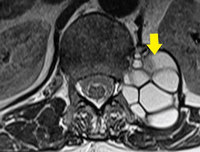

“허리 아파 사진 찍었더니, 웬 포도알 덩어리…” 50대 男, 기생충 가득 주머니였다?